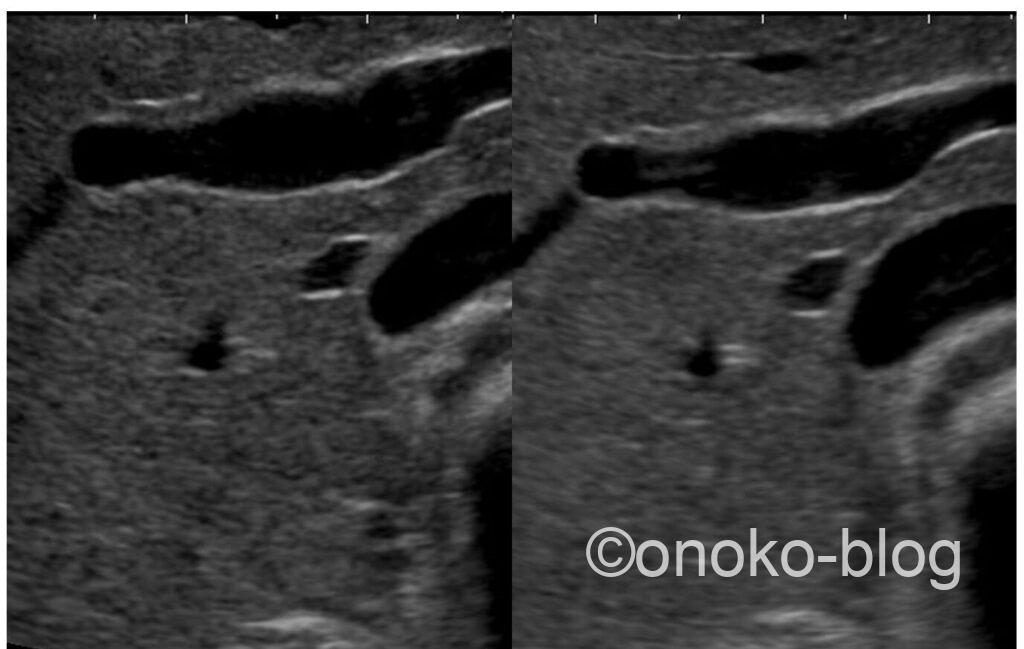

ふたつの画像を並べてみます。

左がWrite Zoom、右がRead Zoomです。こうやって比べてみると違いが分かりますね。